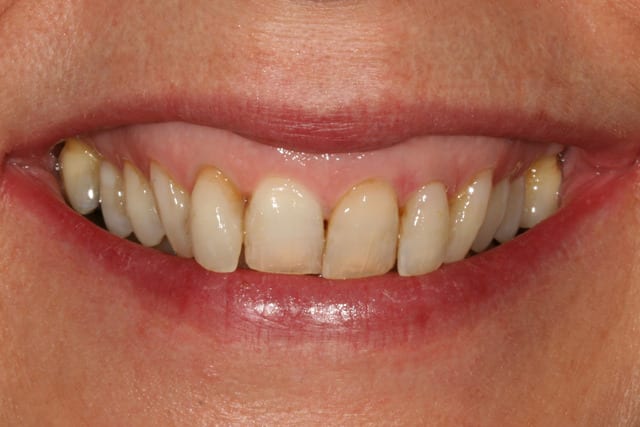

13/07/2011 à 22h44

merci à ceux qui ont participé, vous m'avez fait penser à des choses que je n'avais pas imaginé pour le traitement de ma patiente

et effectivement, si on avait voulu faire un sourire parfait, on aurait pu faire ortho, alignement des collets, facettes, voire une chirurgie de la lèvre pour le sourire gingival

la patiente n'est pas du tout venue pour ça, et je ne me vois pas lancer tout ça pour une patiente qui ne se plaint que de ses composites et un peu de sa 12

je lui ai proposé un éclaircissement, de refaire les compos, et de voir après si on pouvait rentrer la 12 avec un moyen ortho amovible (invisalign, inman aligner ou autre)

puisqu'elle a refusé tout net les bagues

je n'avais pas pensé à corriger sa classe II, ni a tout couronner ou facetter pour "ressortir" les dents très rentrées ; ni même a aligner ses collets en fait.

pour cette patiente qui n'avait pas de grandes exigences, je me suis auto limité en voulant être le moins iatrogène possible.

comme quoi poster m'aura été utile, j'avais pas tout vu ni tout envisagé.

je reste content de mon traitement, tout simplement parce que la patiente est très contente.

elle n'a même pas eu envie d'essayer de bouger la 12 après (et tant mieux parce que maintenant qu'on en a discuté, ça aurait surement été galère de ne toucher que ça)